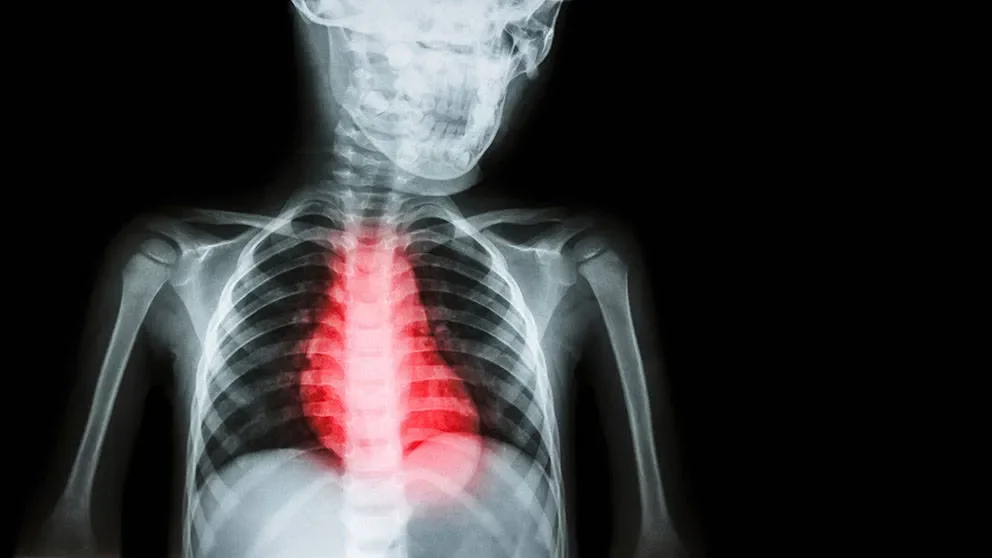

Mutations in one regulatory subunit of AMPK (PRKAG2) can lead to gain of function of AMPK and is associated with heart hypertrophy, specifically left ventricular hypertrophy (LVH). About one percent of patients with unexplained LVH have a PRKAG2 mutation, and clinical progression is poor for these patients. Hypertrophy is seen in other cardiovascular disorders, such as inherited hypertrophic cardiomyopathy (HCM), but the disorders also have important differences. In LVH there are electrophysiologic abnormalities but there is none of the fibrosis seen with HCM.